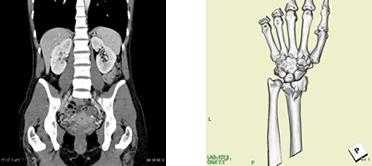

心臓CT検査

当院のCTは、心臓の検査も可能です。造影剤(臓器や血管をよりわかりやすくする薬)を静脈から注射し、心臓の血管を描出して狭窄(狭くなっていないか)を見つけることができます。